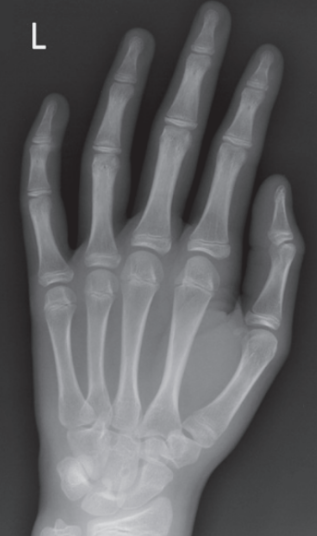

Unequal concavity between phalanges and MCs

Hand was slightly externally rotated

What is wrong with this oblique hand?